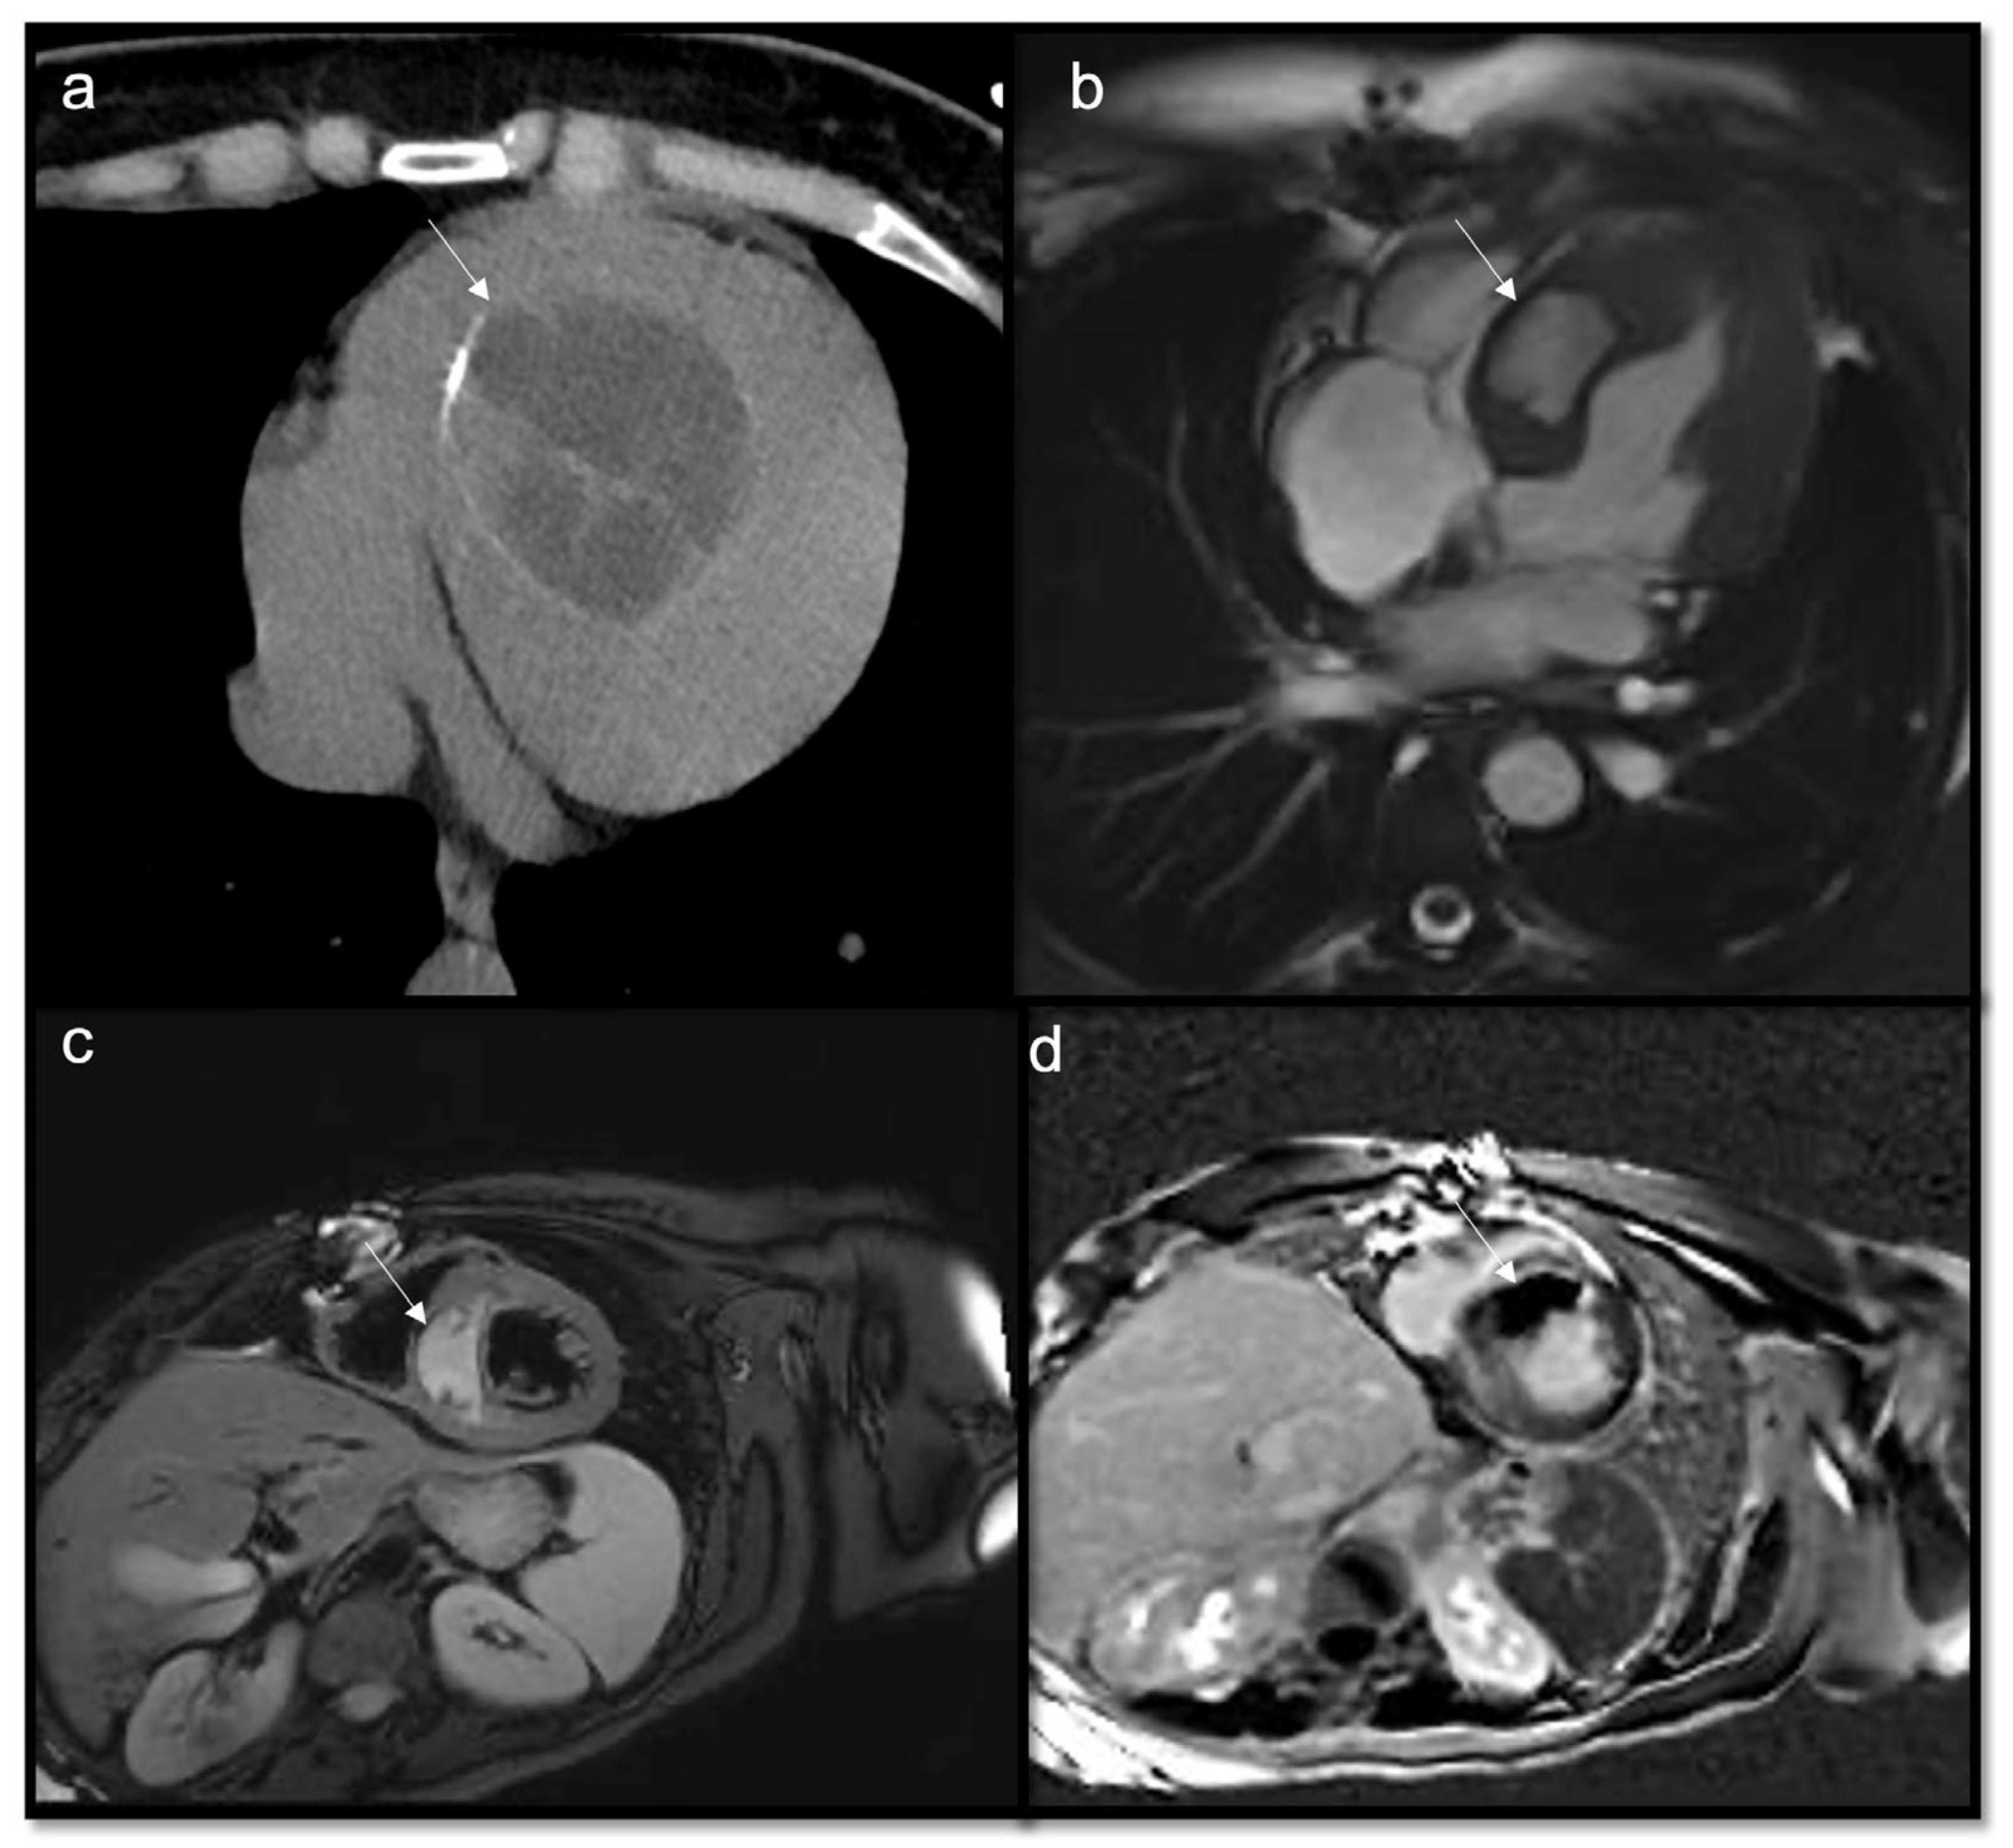

- To recognize fluid content such as a pericardial cyst or myocardial cyst (Figure 3)